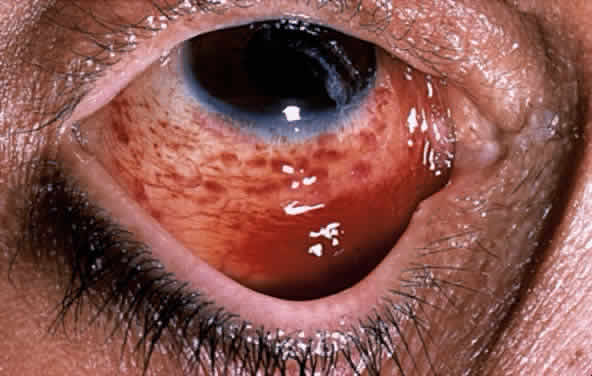

with the acquired immune deficiency syndrome. Ophthalmology 90:859, 1983 120. Shuler JD, Holland GN, Miles SA et al: Kaposi sarcoma of the conjunctiva and eyelids associated with the acquired

immunodeficiency syndrome. Arch Ophthalmol 107:858, 1989 121. Dugel PU, Gill PS, Frangieh GT, Rao NA: Ocular adnexal Kaposi's sarcoma in acquired immunodeficiency syndrome. Am J Ophthalmol 110:500, 1990 122. Dugel PU, Gill PS, Frangieh GT, Rao NA: Treatment of ocular adnexal Kaposi's sarcoma in acquired immune deficiency

syndrome. Ophthalmology 99:1127, 1992 123. Ghabrial R, Quivey JM, Dunn JP Jr, Char DH: Radiation therapy of acquired immunodeficiency syndrome-related Kaposi's

sarcoma of the eyelids and conjunctiva. Arch Ophthalmol 110:1423, 1992 124. Hummer J, Gass JD, Huanga JW: Conjunctival Kaposi's sarcoma treated with interferon α-2a. Am J Ophthalmol 116:502, 1993 125. Offermann MK: HHV-8: a new herpesvirus associated with Kaposi's sarcoma. Trends Microbiol 4:383, 1996 126. Kohn SR: Molluscum contagiosum in patients with acquired immunodeficiency syndrome. Arch Ophthalmol 105:458, 1987 127. Charles NC, Friedberg DN: Epibulbar molluscum contagiosum in acquired immune deficiency syndrome: case